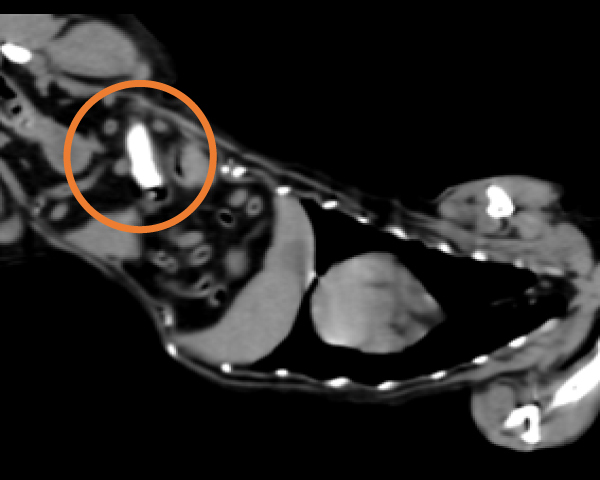

造影CT検査にて腫瘤の浸潤を評価